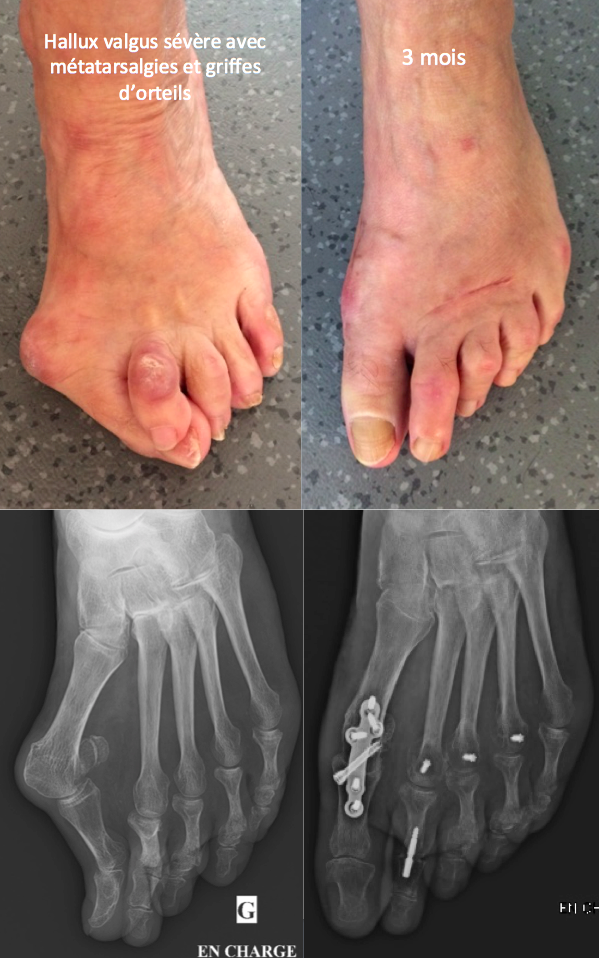

Aux différents degrés de déformation correspondent différentes techniques chirurgicales permettant de la corriger, de l’ostéotomie courte mini-invasive à l’arthrodèse métatarso phalangienne.

Voici quelques photos avant et 3 mois après la chirurgie :